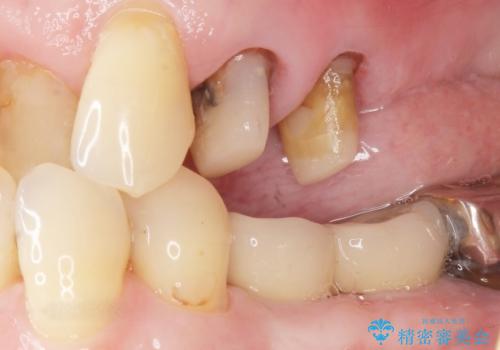

精査したところ、左上の大臼歯2本(左上67)が欠損しており、左上の小臼歯2本(左上45)は根が短く動揺があり根尖病変を認めました。

「大臼歯は入れ歯かインプラントを検討しているがまだやりたくないため、小臼歯のみを治療してほしい」との患者様のご希望により、

相談を重ねた上で小臼歯2本の再根管治療と連結補綴を行いました。